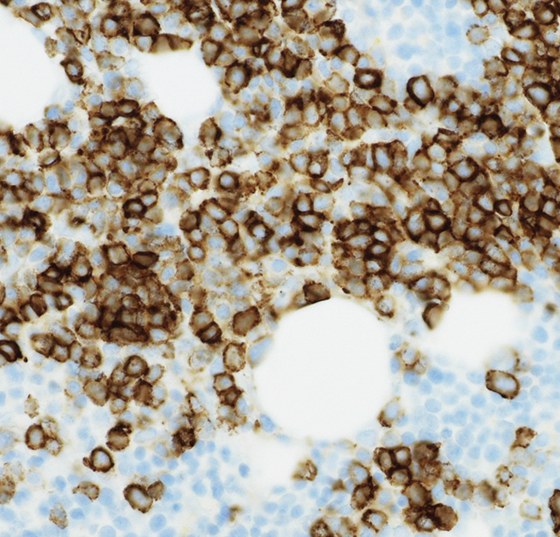

• Multiples Myelom (MM)

Prognostische Faktoren, die Rolle von Leptin und MGUS im Fokus

Das Multiple Myelom entsteht durch die Entartung einer einzigen Plasmazelle, deren Klone sich im Knochenmark ausbreiten. Insgesamt tritt die Erkrankung nur sehr selten auf. Allerdings gehört sie zu den häufigsten...…